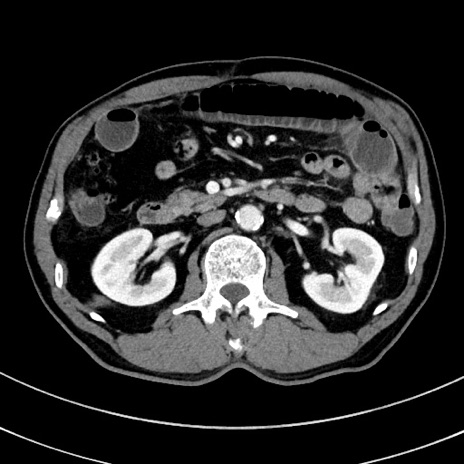

冠状断像

【症例】 60歳代男性

【主訴】 黒色吐物

【現病歴】 4日前から嘔気自覚、2日前の朝食後にも嘔気あり、自分で手で嘔吐反射起こし嘔吐したところ血が混ざっていたため受診。

【既往歴】 5年前汎発性腹膜炎を伴う急性虫垂炎で手術、高血圧、前立腺肥大症、高脂血症

【身体所見】 腹部正中に手術癩痕あり 腹部平坦・軟圧痛なし膨満感あり

【データ】WBC 8400、CRP 4.54